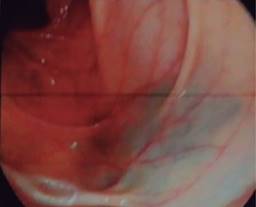

Se le realiza ultrasonido (USG) abdominal que reporta imagen de tumor en fosa iliaca derecha con medidas de 10.5 × 5.5 × 9.9 cm. El estudio de colonoscopia no muestra evidencia de tumor en recto y colon, se observa aparente compresión extrínseca a nivel de orificio de válvula ileocecal (Figura 1).